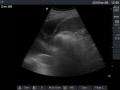

Chest computed tomography is more accurate for diagnosis and may be obtained to better characterize the presence, size, and characteristics of a pleural effusion. Lung ultrasound, nearly as accurate as CT and more accurate than chest X-ray, is increasingly being used at the point of care to diagnose pleural effusions, with the advantage that it is a safe, dynamic, and repeatable imaging modality.[7]

The lung expanding within an area of pleural effusion as seen by ultrasound